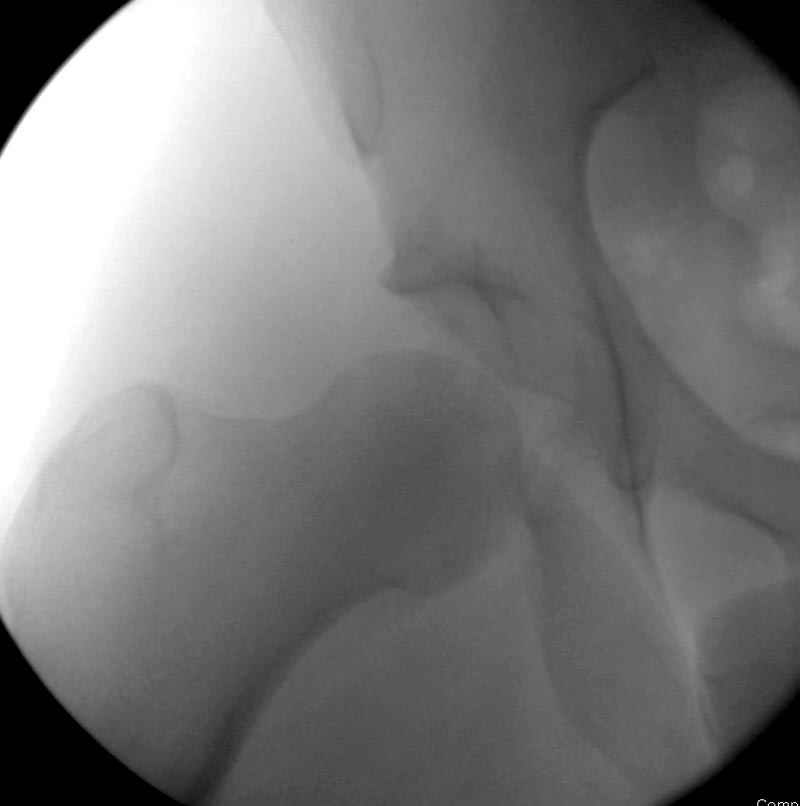

7:30 начало операции, больной на спине, попытка репозиции после анестезии N3, укладка больного на боку, доступ Kocher- Langenbeck, состояние седалищнего нерва около 2.5см кровоподтек, через joistick головка бедра приподнята, освобовождение сустава, фрагмент заднего края более 3х4 см репонирован на свое место. После промывания

сустава, репозиция вывиха (N4), фиксация фрагмента 2.7(4) мм шурупами и допольнительно реконструктивной пластиной на 8 дырок, фиксация 3.5мм шурупами проксимально и дистально.

Интраоперционные N5 косая запирательная и N6 подвздошный снимок

11:50 больной в послеоперационной, рентгенограмма N7, компьютерная томограмма в тот же день N8-10